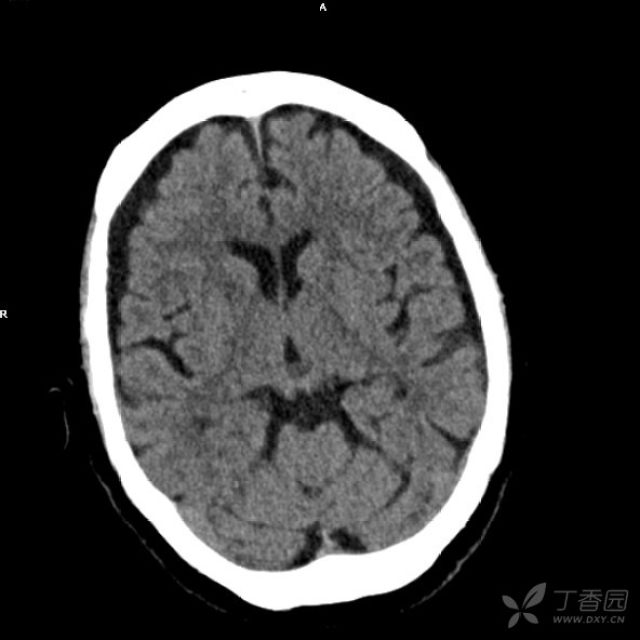

典型松果体囊肿?

病例学习:肝性脑病的诊断要点

从 MRI 来识别 肝性脑病